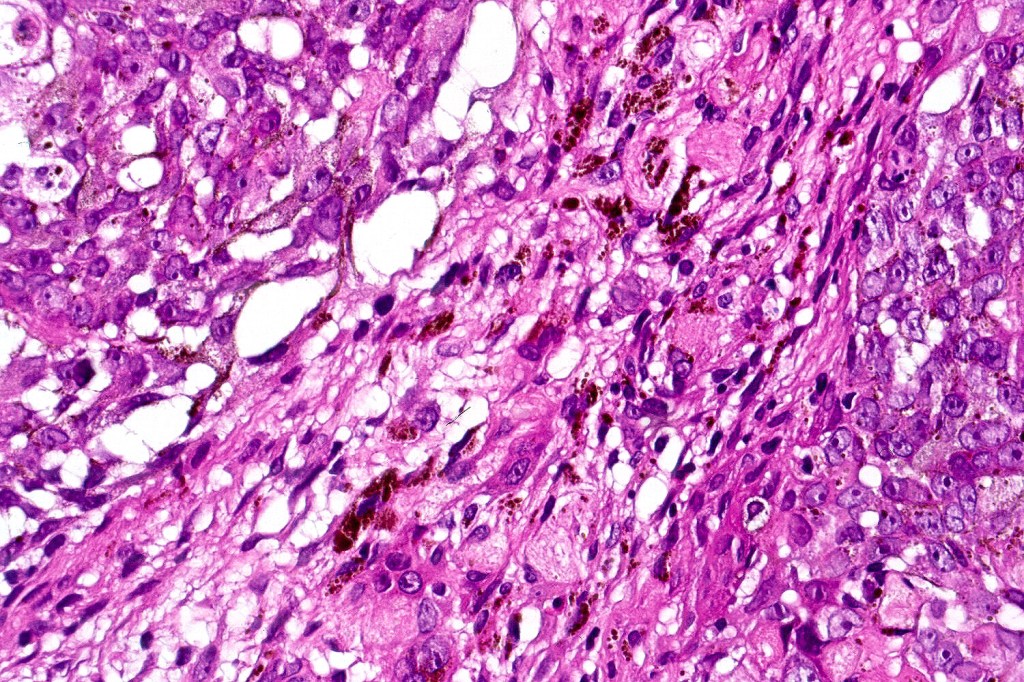

•Basaloid population with prominent nucleoli accompanied by supramatricial and ghost cells

•Variable pleomorphism

•Mitoses may be conspicuous

•Heavily pigmented dendritic +/- epithelioid melanocytes

Often solar elastosis is marked